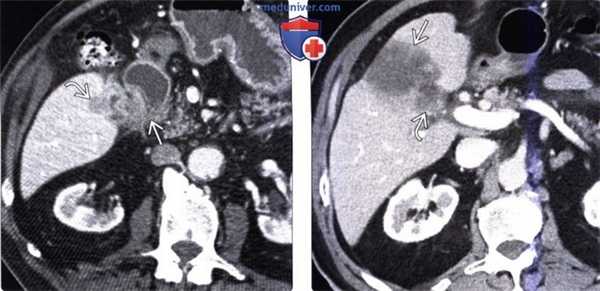

(Слева) На аксиальной КТ с контрастным усилением определяется рак желчного пузыря с инвазией в печень и нисходящую часть двенадцатиперстной кишки. Такие опухоли, если признаются резектабельными, однозначно требуют выполнения расширенной холецистэктомии и радикальной резекции.

(Справа) На аксиальной КТ с контрастным усилением визуализируется объемное образование в ямке желчного пузыря, прорастающее в печень. Во многих случаях, в том числе и в этом, место происхождения опухоли сложно определить.

(Слева) На аксиальной КТ с контрастным усилением определяется распространенное круговое утолщение стенки желчного пузыря, которое проспективно было расценено как проявление ксантогранулематозного холецистита. Тем не менее, во время оперативного вмешательства обнаружился рак желчного пузыря.

(Справа) На сонограмме визуализируется объемное образование в ямке желчного пузыря и конкрементдающий акустическую тень. Образование не отделено от прилежащих отделов печени. На КТ (томограммы не продемонстрированы) была обнаружена локальная инвазия рака желчного пузыря в центральные отделы печени.

(Слева) На аксиальной КТ с контрастным усилением определяется выраженное неравномерное утолщение стенки желчного пузыря, непосредственная инвазия печени, а также перипанкреатическая/портокавальная и забрюшинная лимфаденопатия. Увеличение лимфатических узлов этих групп является типичным проявлением рака желчного пузыря.

(Справа) На аксиальной КТ с контрастным усилением визуализируется большое гиподенсное образование в печени. Это образование может быть опухолью печени, однако желчный камень в его центре и невозможность визуализации желчного пузыря позволяют предположить, что образование представляет собой рак желчного пузыря с инвазией печени.